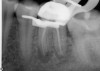

Excellent diagnosis essentially begins with two fundamental components: a doctor willing to listen to the patient’s chief complaint, and proper diagnostic tools. Among the most important tools are a precise periapical radiograph (PA) and bitewing (BW). Although a PA is often enough to provide an accurate portrayal of the patient’s condition, sometimes it alone does not suffice. Figure 1, Figure 2, and Figure 3 demonstrate a case that illustrates this point clearly. Despite two acceptable PAs (Figure 1 and Figure 2), it is difficult to assess the source of the patient’s pain to temperature. However, the BW radiograph Figure 3 provides significantly more clarity than either of the two PAs. The BW depicts localized bone loss (around tooth No. 2), a pulp stone (No. 2), a flat occlusion, numerous calcified canals, multiple restorations in tooth No. 30, and gross decay especially on tooth No. 3, which is the source of the patient’s pain to temperature. In this instance these images depict how much more useful a BW can be than just a conventional PA.

Fig 2. Acceptable PA radiograph.

Figure 2